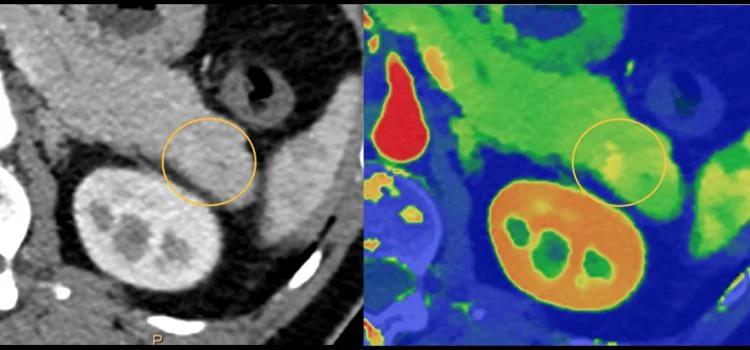

在肿瘤成像方面, 能量CT可非常精准地识别超早期肿瘤病灶 。

比如肺结节诊断,除了形态学的大小、密度、体积等参数,能量CT还可以获取碘的摄取率以及代谢程度, 对于肺结节的定性提供更多诊断信息 。

光谱CT 检测肺结节